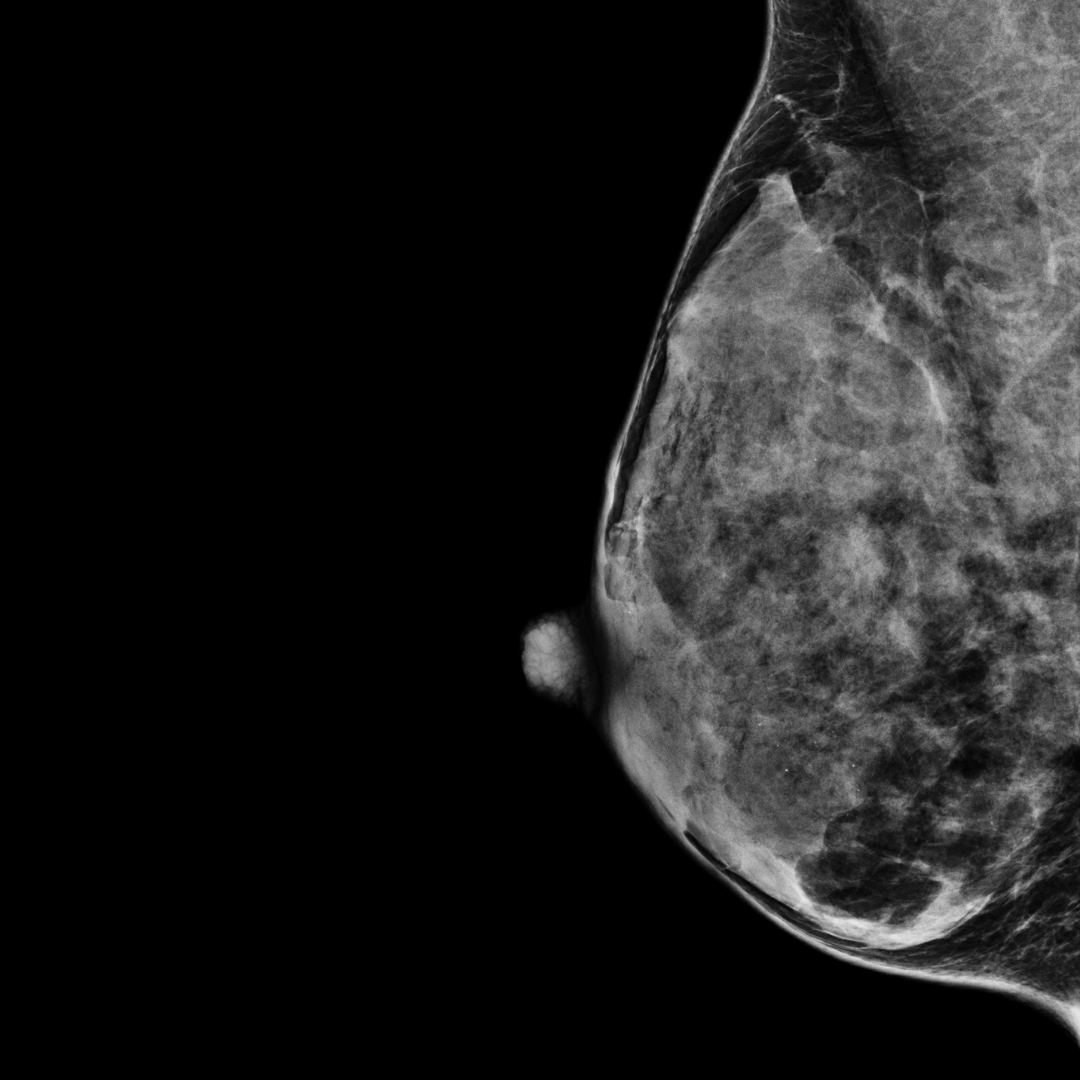

Category D

(most dense)

BI-RADS category D:

The breasts are extremely dense.